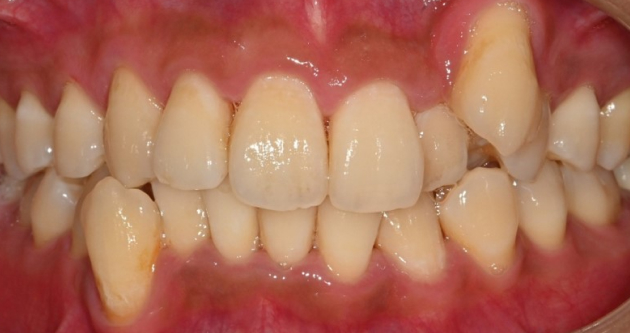

실제 사례 Before & After

바른선택치과의원은 결과로 증명합니다. 기능과 심미 모두 찾은 바른선택치과의원 실제 환자 케이스를 확인해보세요.

before Before

after After

치료 시작 전 촬영 2025.02.18 | 치료 완료 후 촬영 2025.02.28

※ 바른선택치과의원은 의료법을 준수하며 위 케이스는 실제 내원 환자분의 동의하에 공개된 사진과 동일한 환자분께 같은 조건에서 촬영한 사진을 활용했습니다.

개인에 따라 진료 및 치료 방법이 다르게 적용할 수 있으며, 효과와 부작용이 개인마다 다르게 나타날 수 있는 점을 안내해 드리며, 진료 전 전문의료진과 충분한 상담을 권해드립니다.